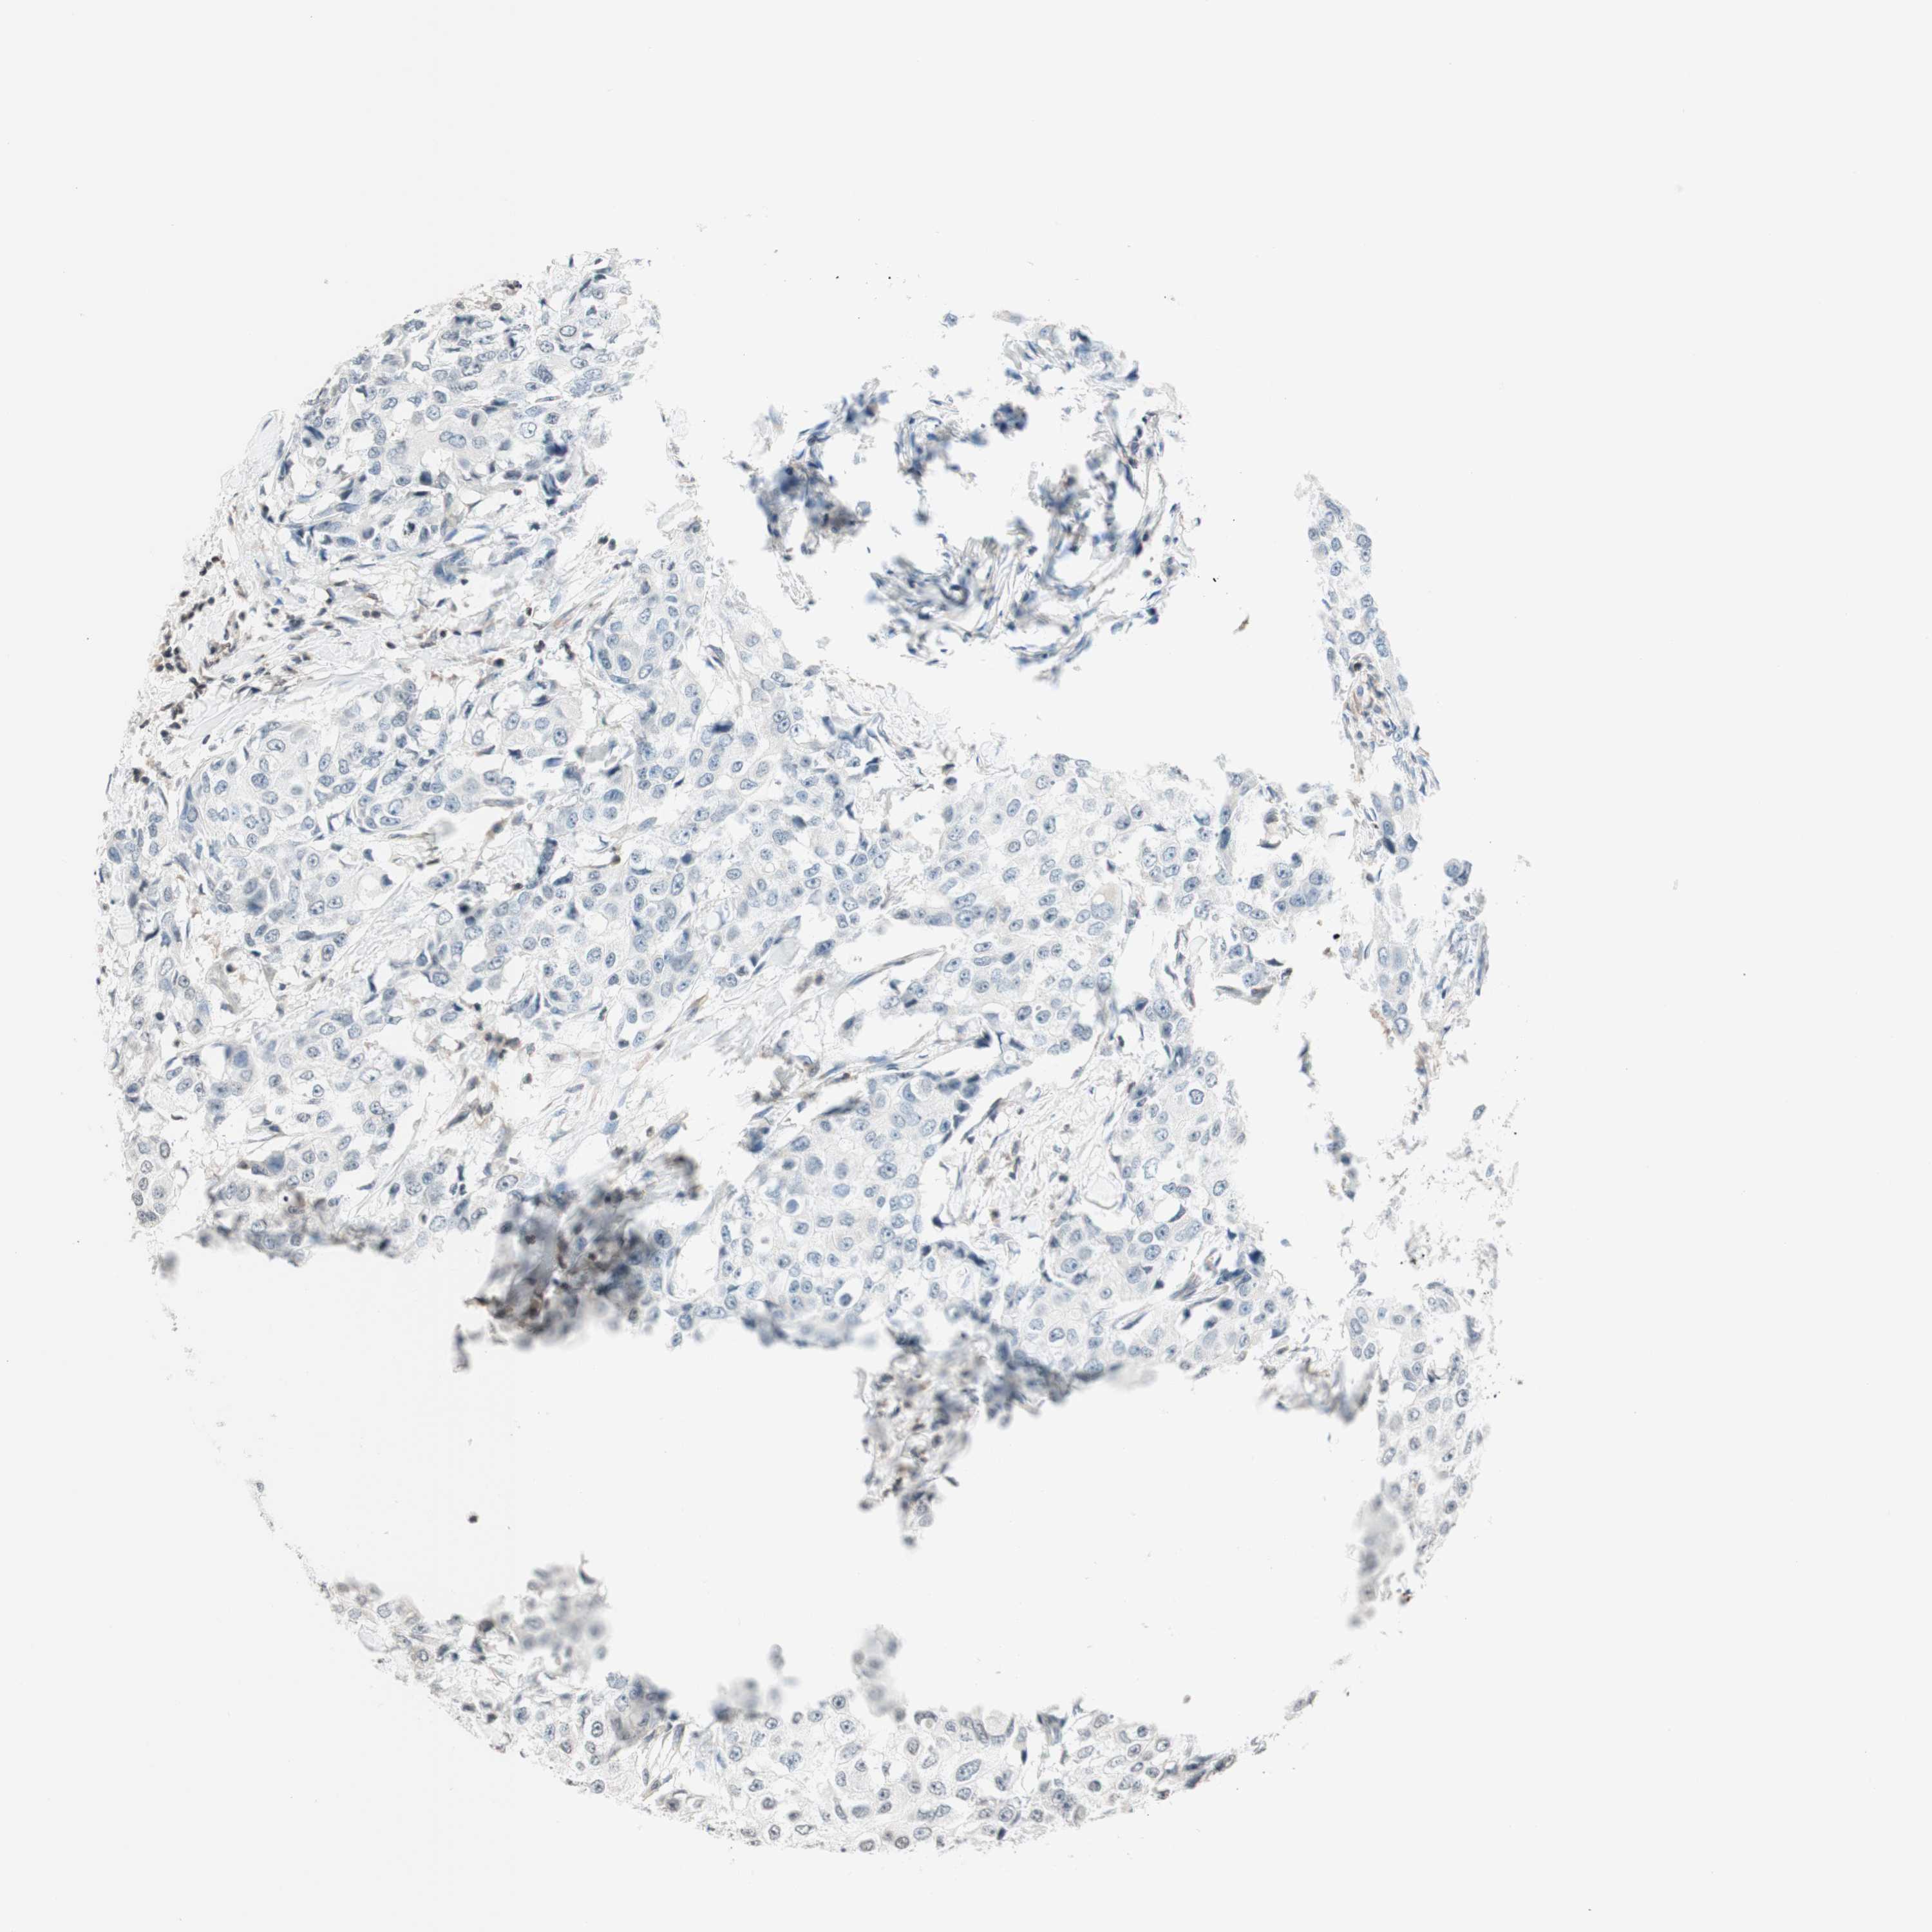

BRCA TCGA BRCA VALIDATION PROTEIN EXPRESSION

ANTIBODIES

AND

VALIDATION